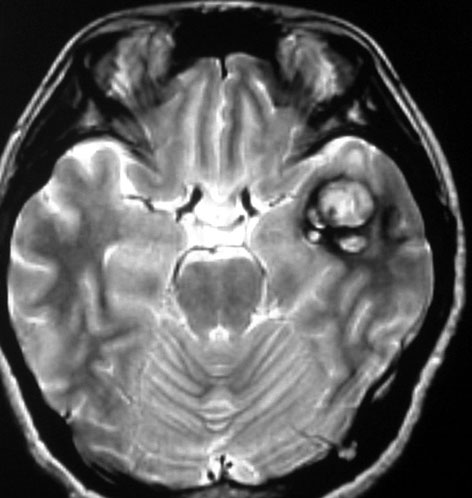

左上のT2*でみられるように多発性海綿状血管腫の成人男性に発生した中脳海綿状血管腫です。複視と歩行失調で発症して,数回の脳幹部出血を繰り返し,水頭症になったために第3脳室開窓術がなされました。それでも出血は止まらず、両側の動眼神経麻痺による両側眼瞼下垂,歩行失調,嚥下障害などさまざまな中脳症状が進行しました。

しかたがないので手術で摘出しました。なんとか眼瞼が持ち上がるようになり歩行も可能で嚥下もできます。幸いだったのは感覚路(脊髄視床路)の障害による体性疼痛が生じなかったことです。